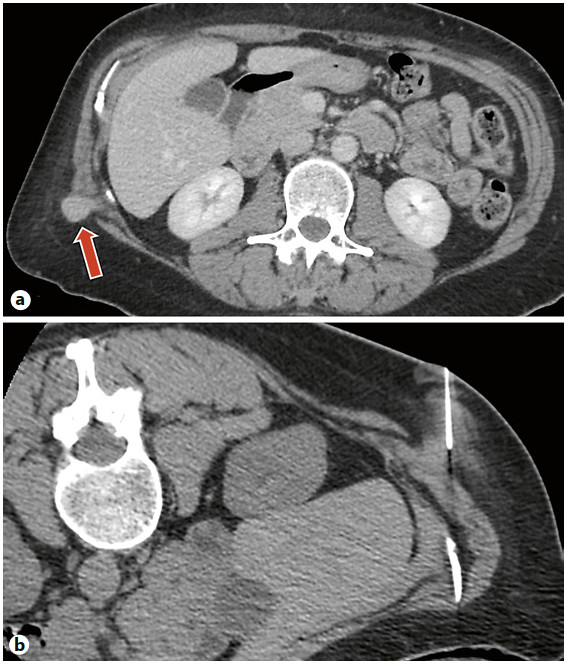

Results: Cryoablation of this mass was successful with no complications. CT images during the procedure demonstrated circumferential coverage of the entire lesion with no injury to the surrounding tissues.